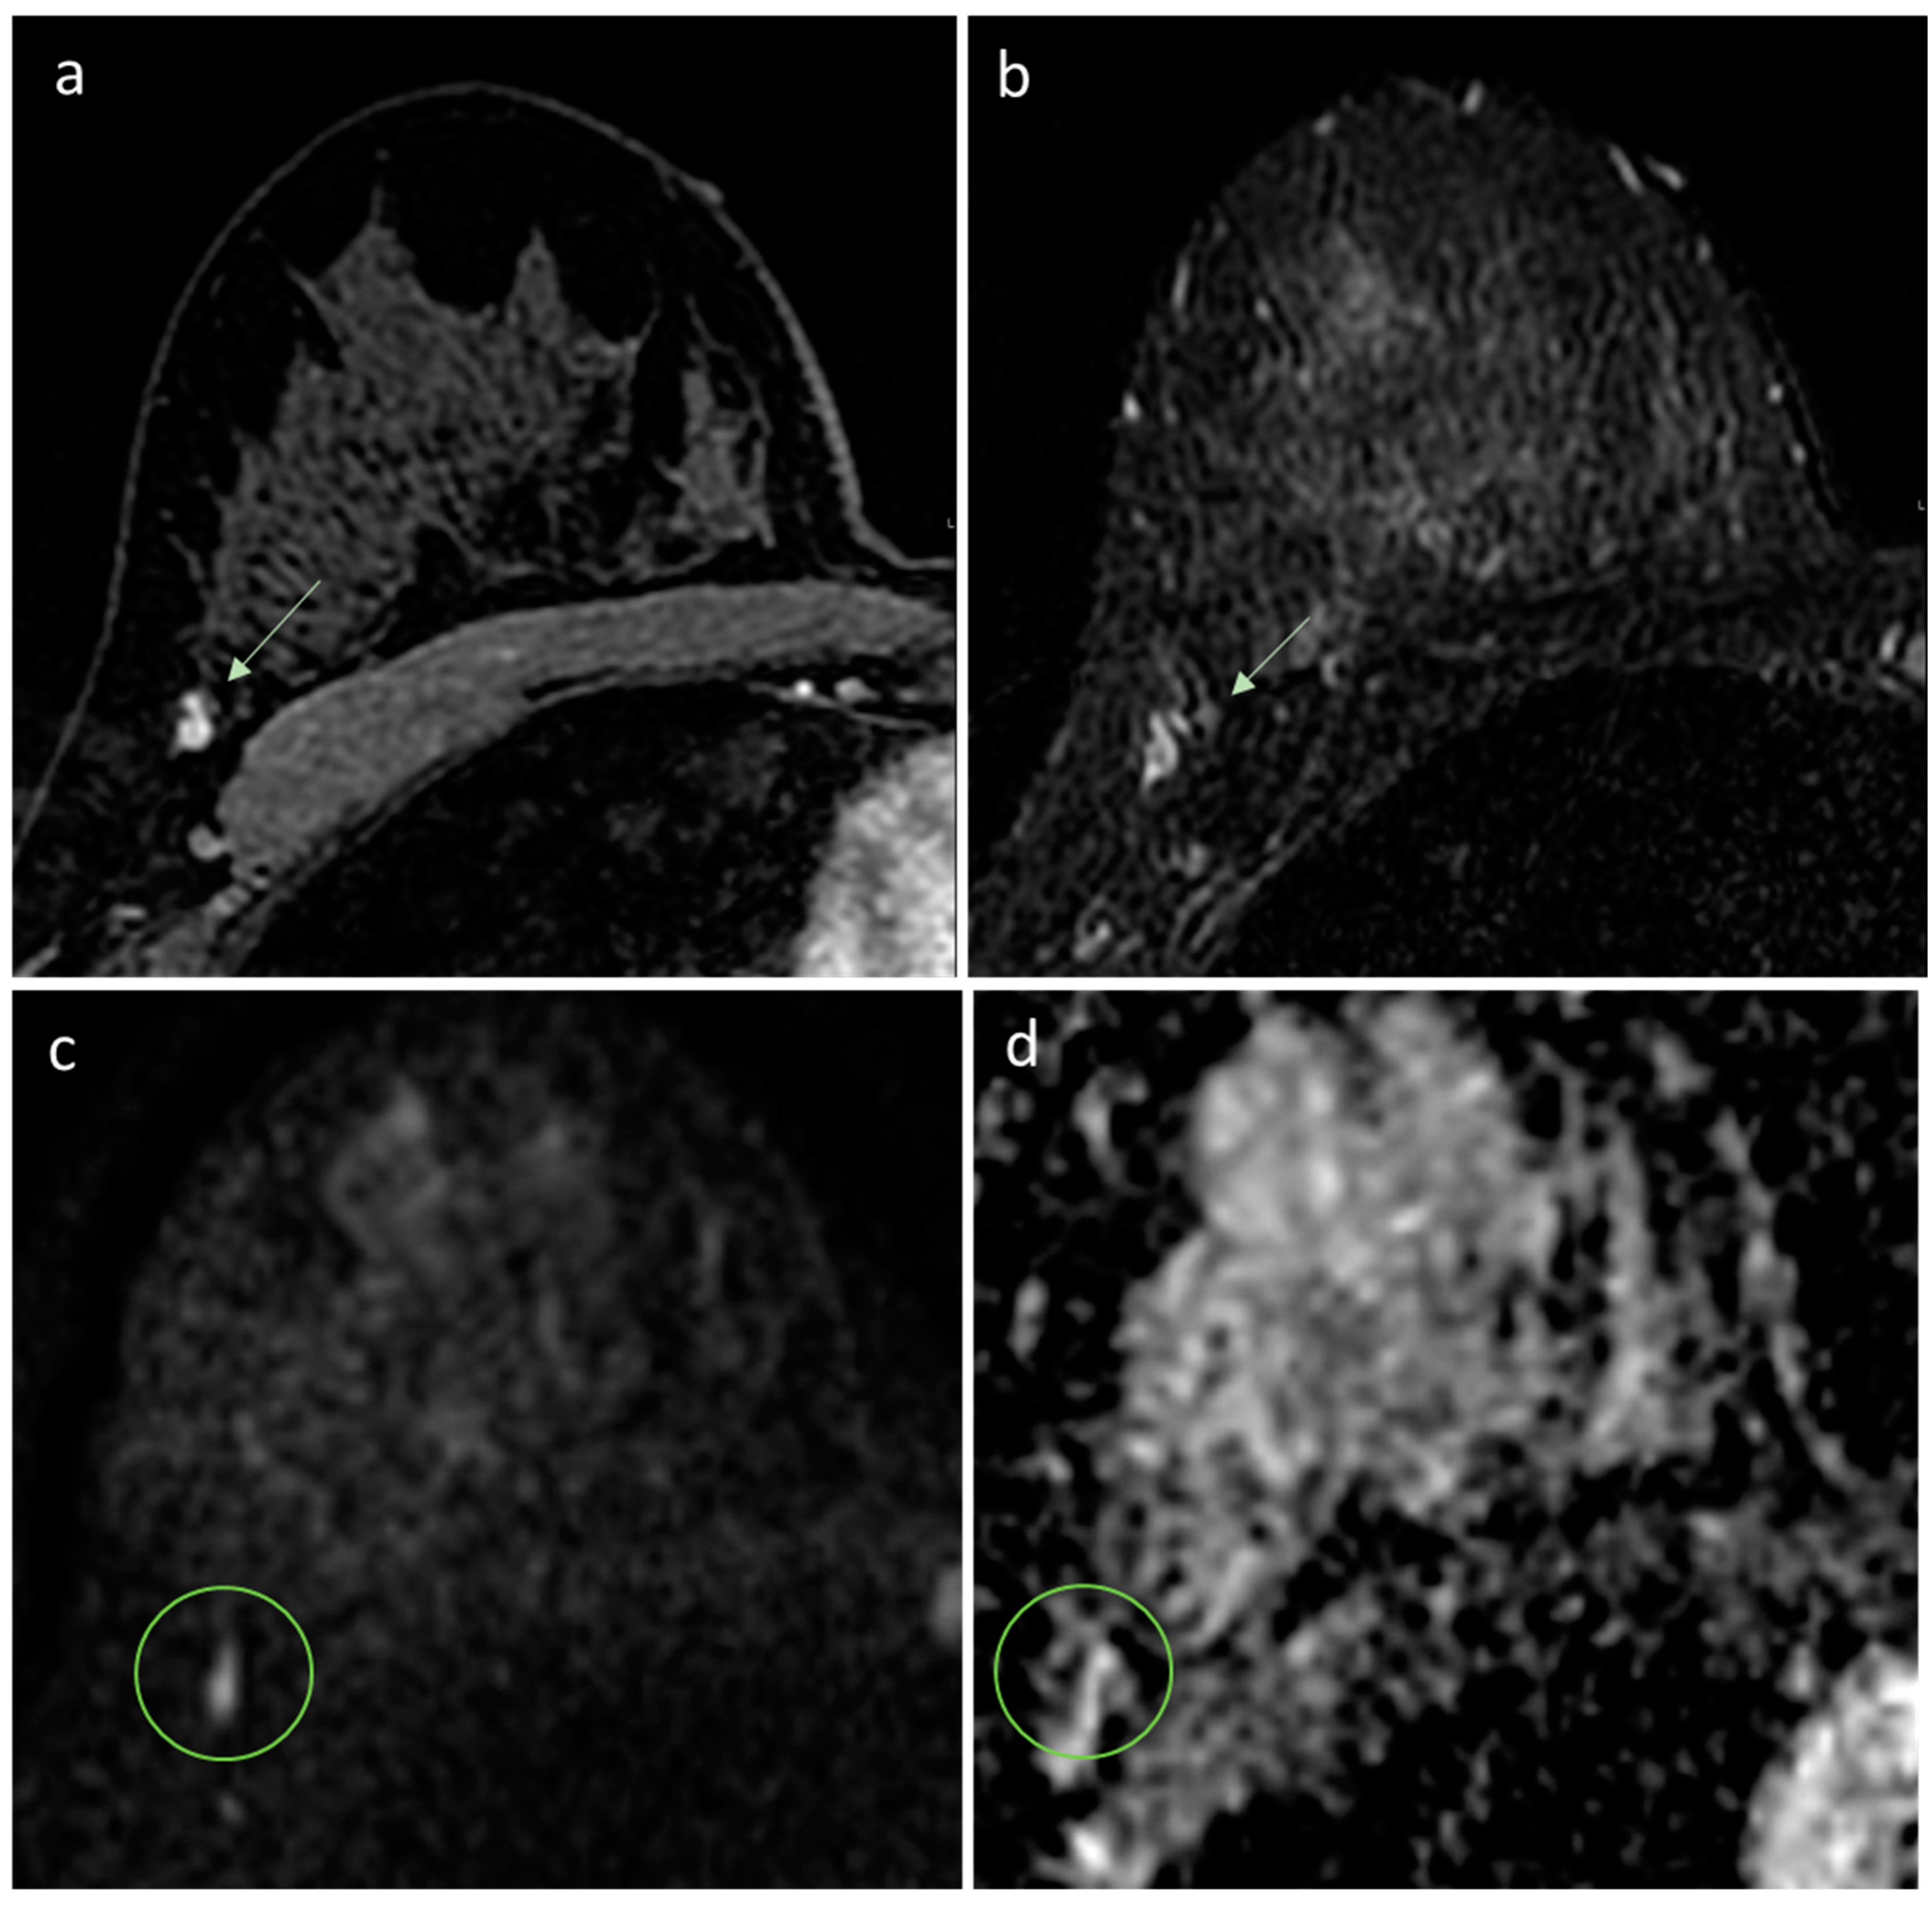

- Pesapane, F.; Rotili, A.; Penco, S.; Montesano, M.; Agazzi, G.M.; Dominelli, V.; Trentin, C.; Pizzamiglio, M.; Cassano, E. Inter-Reader Agreement of Diffusion-Weighted Magnetic Resonance Imaging for Breast Cancer Detection: A Multi-Reader Retrospective Study. Cancers 2021, 13, 1978. [Google Scholar] [CrossRef] [PubMed]